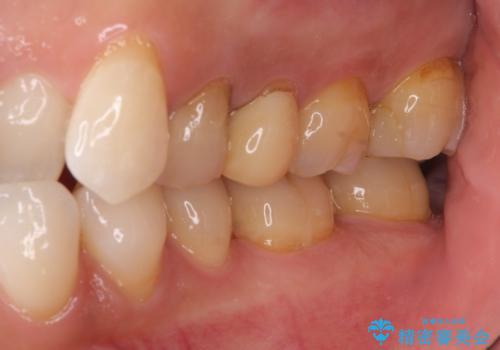

体調が悪いと腫れる 根管治療とセラミック治療

- 2年ほど放置していた左上の仮歯がとれたことをきっかけにご来院された患者様です。

セラミック治療がご希望でしたが、ときどき歯肉が腫れるということで根管治療もご希望されました。

左上で効果を実感して頂き、その後右上もご希望されました。合計3本の歯を治療しました。

左上の仮歯を2年使用して穴があいて外れたことをきっかけにご来院されました。

腫れもなくなり、見た目もきれいになったため、右上もご希望されて計3本の歯を治療しました。患者様には大変満足して頂きました。